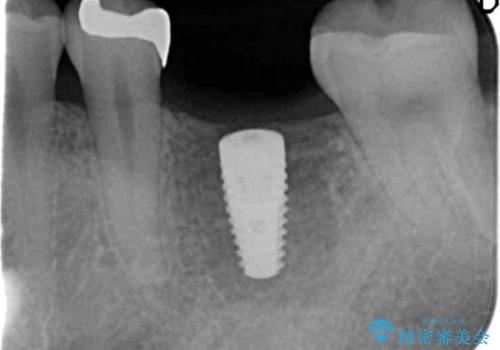

抜歯後ブリッジとインプラント治療を検討・相談し、より周囲の歯を削らずに済むインプラント治療を希望されたのでインプラントによる機能回復を計画します。

- 46.2万円(インプラント・チタンカスタムアバットメント・仮歯・ジルコニアクラウン)費用は治療当時の料金となります